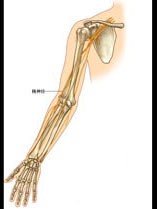

肘部桡神经(如图)损伤的症状、体征有哪些()

A:不能伸腕

B:大鱼际萎缩

C:拇指不能内收

D:拇指不能背伸

E:虎口区感觉障碍